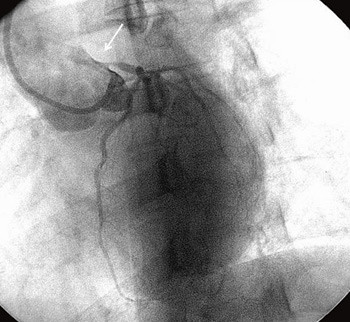

Hun hadde fått påvist Hodgkins sykdom i 1991 og ble da behandlet med cellegift og senere konsoliderende stråleterapi. Cellegift ble gitt i form av antracyklinet epirubicin totalt 360 mg, videre bleomycin, oncovin og dacarbazin (EBOD-kurer). Stråleterapi ble gitt som kappefelt, 23 behandlinger à 1,8 Gy, totalt 41,4 Gy. Strålefeltet inkluderte collum, supra- og infraklavikulære områder bilateralt og mediastinum inkludert hjertet (fig 1). Regelmessige kontroller avdekket ikke tegn til residiv.

Ekkokardiografi ble gjort med puls 99 og viste en normal venstre ventrikkel med ejeksjonsfraksjon ca. 50 %. Det ble ikke sett tegn til hypertrofi eller kardiomyopati. Det forelå en mindre lekkasje i aortaklaffen. Diagnosen koronarsykdom ble styrket, og det ble startet behandling med betablokker i form av metoprolol samt acetylsalisylsyre. De anstrengelsesutløste brystsmertene bedret seg etter at hun begynte med metoprolol. Koronar angiografi viste høygradig stenose i venstre hovedstamme, og uttalte stenoser både i a. circumflexa og i a. descendens anterior (fig 2). I høyre koronararterie var det signifikante stenoser både proksimalt og perifert. Hun ble operert med aortokoronar bypasskirurgi. Det postoperative forløpet ble komplisert med perikardeksudat og pleuravæske, men senere har forløpet vært ukomplisert. De anstrengelsesutløste brystsmertene har forsvunnet, og hun er tilbake i full jobb.

Strålebehandling mot thorax ved Hodgkins sykdom eller andre kreftformer bedrer overlevelsen, men behandlingen kan blant annet gi utvikling av prematur koronarsykdom (6), klaffesykdom (7) eller kronisk perikarditt (8). Flere grupper har beskrevet sammenheng mellom tradisjonelle risikofaktorer og stråleterapi mot mediastinum for utvikling av kransåresykdom (9, 10). Selv om dette er historiske data, er de aktuelle fordi pasienter med Hodgkins sykdom har lang forventet levetid. I dag gis mer moderne stråleterapi med lavere totaldoser, men det er uavklart hvordan dette vil påvirke risikoen for utvikling av kransåresykdom. Vår pasient hadde familiær disposisjon for prematur koronarsykdom og røykte daglig. Det er nærliggende å anta at strålebehandlingen 15 år tidligere kan ha bidratt til den utbredte koronarsykdommen i en alder av bare 34 år. Karakteristiske forandringer i koronararteriene ved stråleskade er ostielesjoner både i venstre og høyre koronararterie, som hos vår pasient, og mer diffuse og lange stenoser med glatt overflate bedømt angiografisk (11).